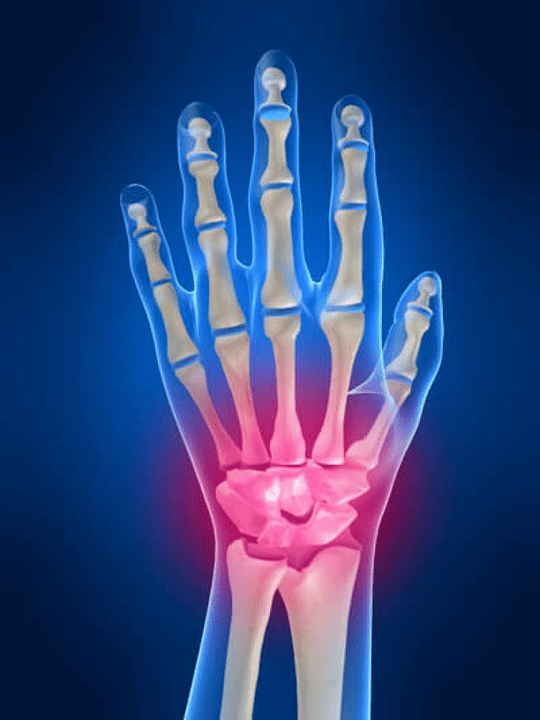

Die Artikulation des Handgelenks

Die Artikulation des Handgelenks besteht aus den Knochen der proximalen Knochen (Vorgesetzter) eine Reihe von Handgelenken (Trihedralknochen, Samen -Moon, Rumpf) und distale Bereiche der Strahlung und der Ellbogenknochen. Der Ellbogenknochen ist nicht direkt mit den Knochen des Handgelenks verbunden, sondern mit Hilfe von Distal (Minderwertig) die gemeinsame Scheibe. Diese Struktur trennt den Hohlraum des Absturzes des Handgelenks von der distalen Hohlraum (Minderwertig) Die Artikulation der Fliesen.